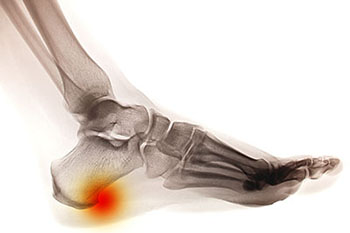

Heel spurs are essentially a hook of bone that forms at the back of the foot, at the base of the ankle. Heel spurs are also described as a calcium deposit that covers the tendons and ligaments of the ankle. Heel spurs cause extreme pain, and can prevent someone from walking or being physically active at a normal level.

Treatment of heel spurs can be treated many ways and most often times is very effective. If someone suspects that they have heel spurs, they should contact their physician. Their physician will recommend that they perform an x-ray on the patient's ankles. The physician may also perform a physical on the patient to ensure that there are no underlying conditions, and of course if heel spurs are discovered a physician can recommend treatment options.